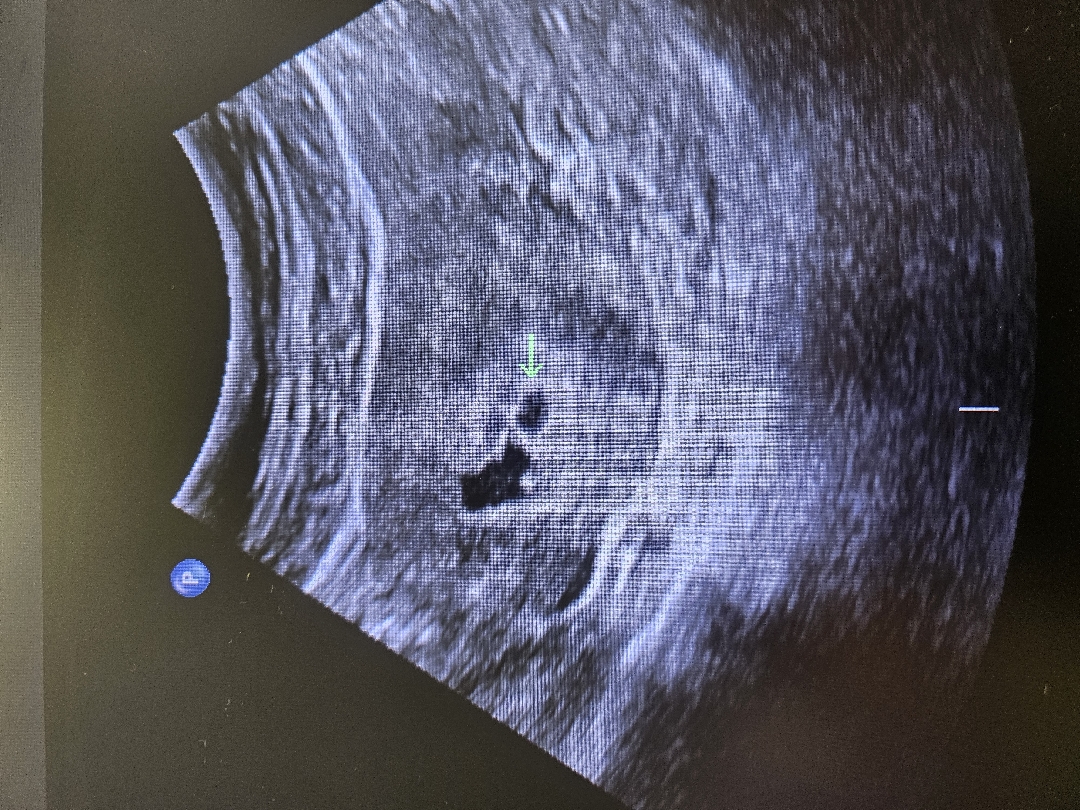

오늘딱 5주에요 초기에 피고임 ,물고임 있을순있다고 들었는데 걱정되네요 ㅠ 애기집옆에 2cm가량있어요 선홍색피는안나구 생리끝물처럼 갈색살짝묻어나와요 병원에선 빨갛게 나오는거아님 괜찮다고그러는데 걱정걱정 ,,, 초록화살표가 애기집이고 왼쪽이 액체고임이에요